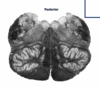

29

ID the level

Midbrain

30

Medulla

31

Pons